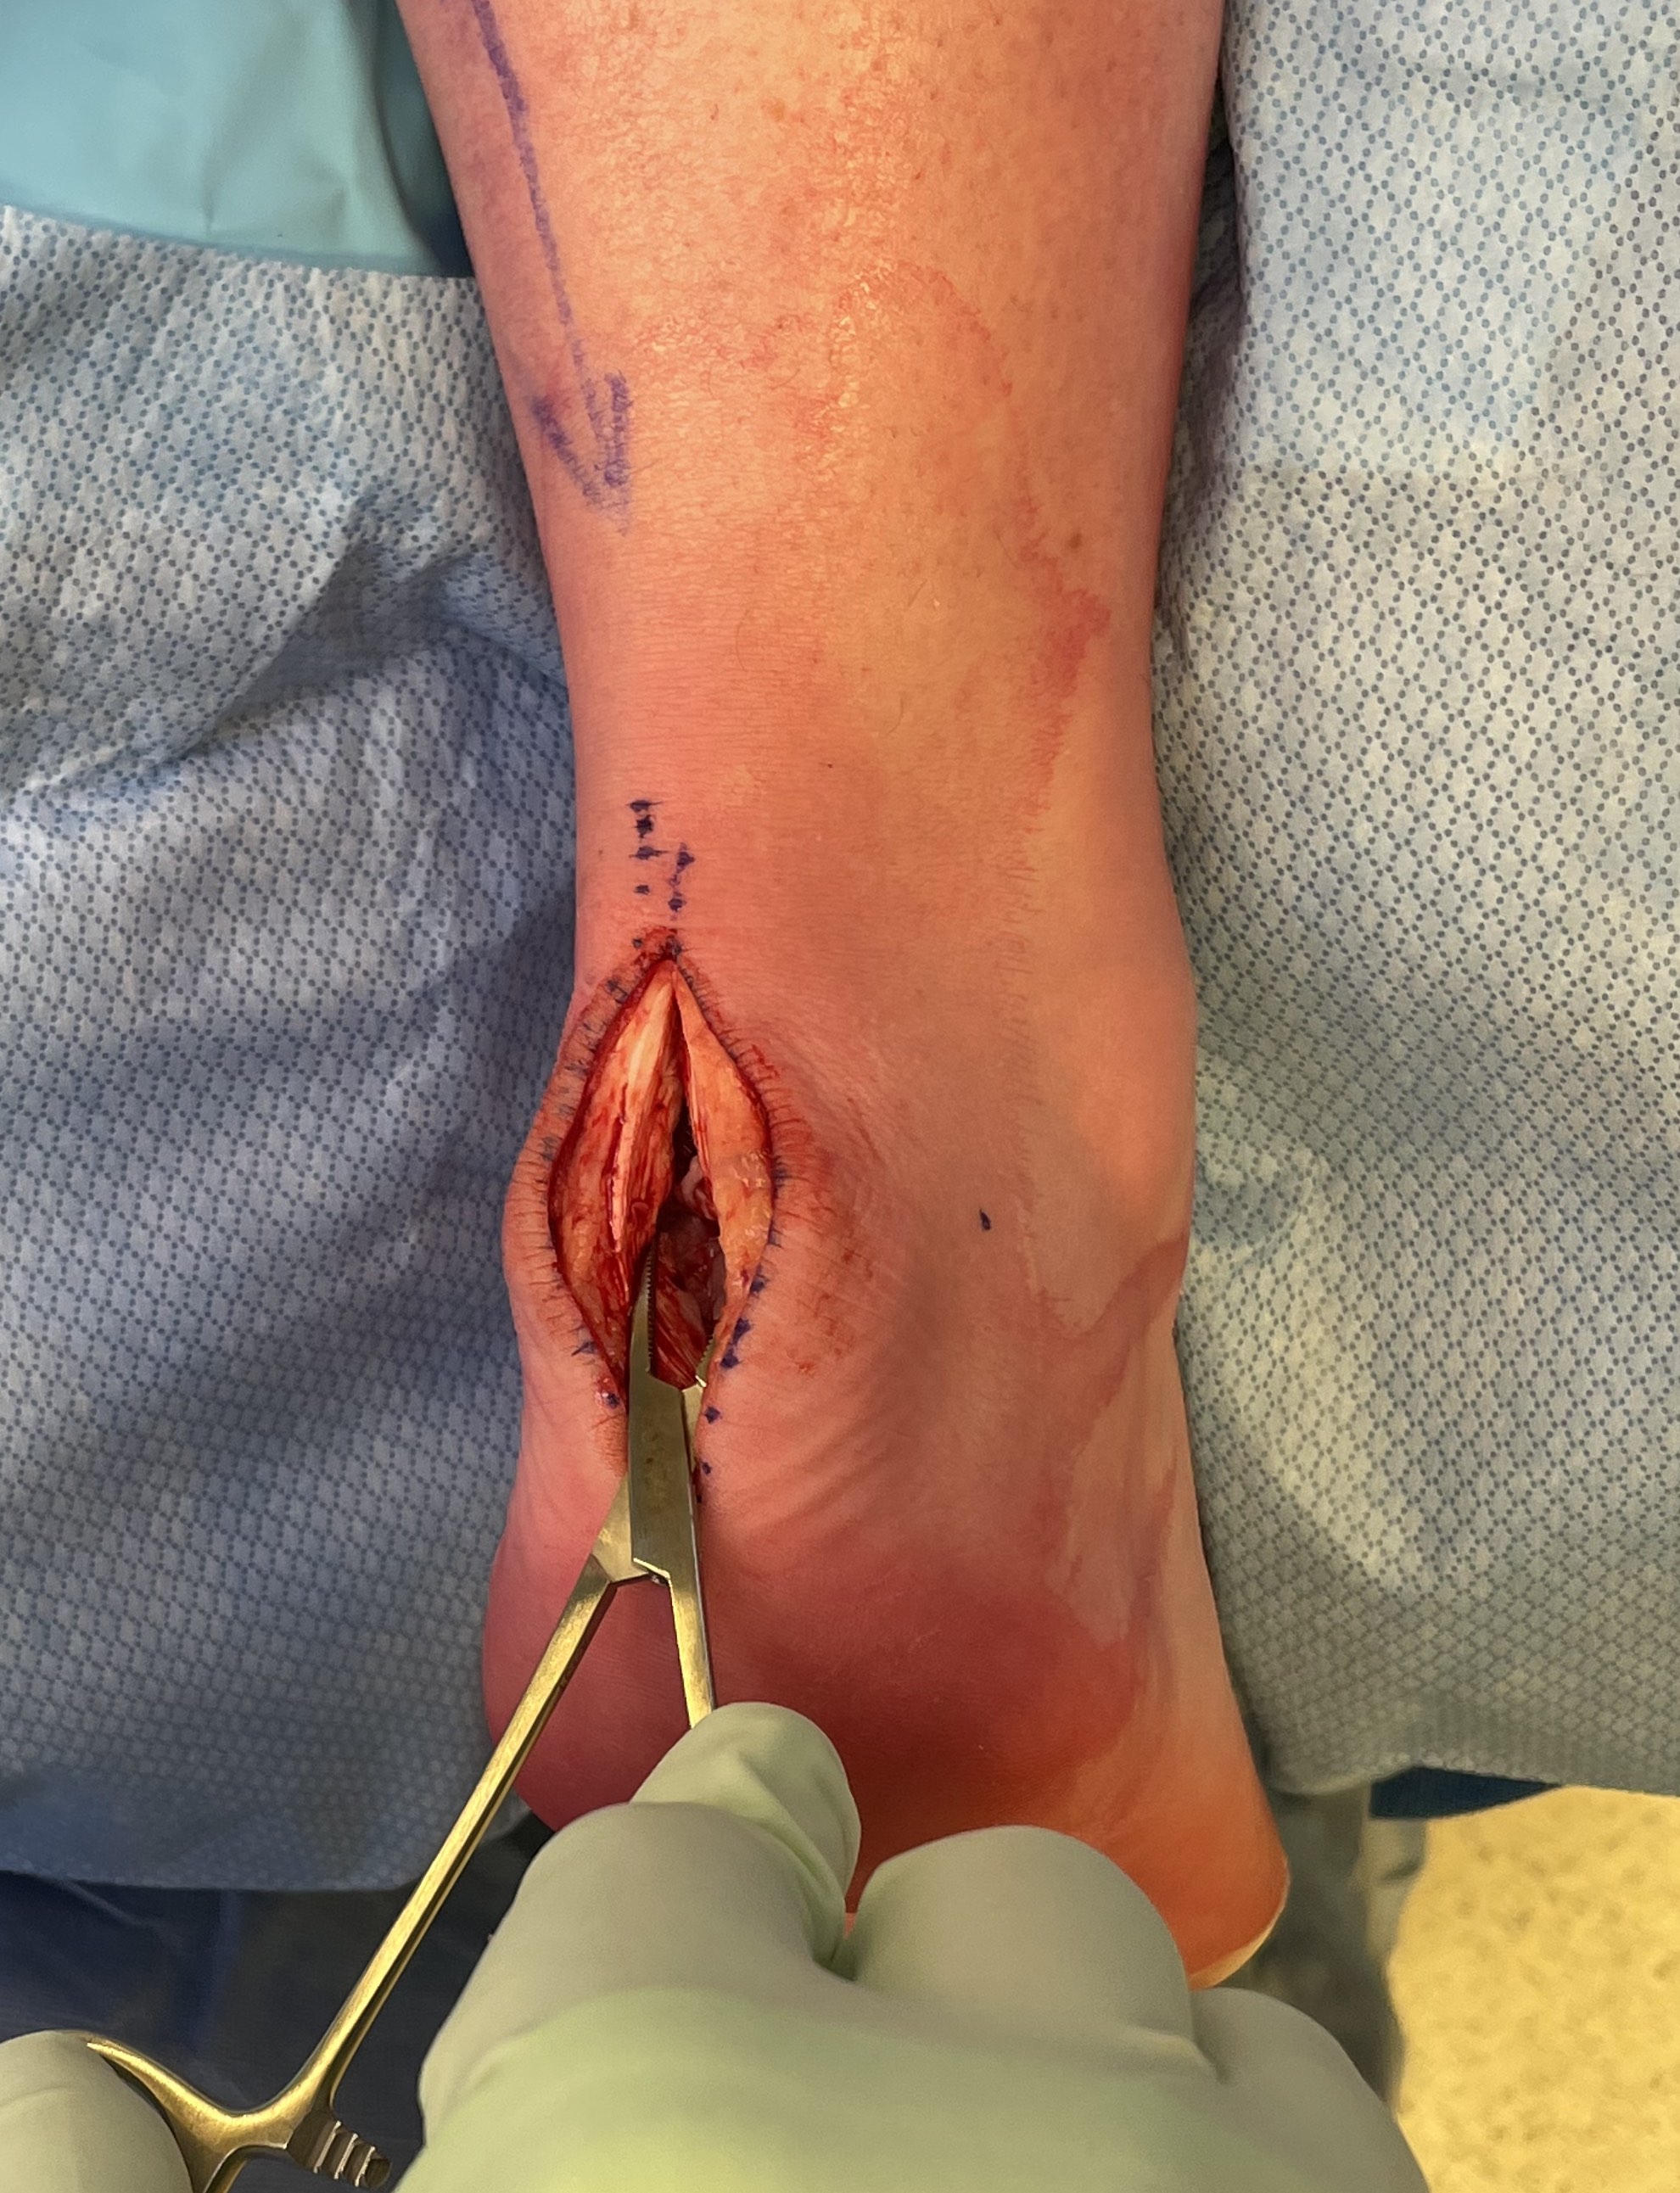

Technique

Arthrex - Achilles SpeedBridge™ System

Vudmedi surgical technique video

Patient prone

- elevate ankle to allow dorsiflexion

- identify and preserve sural nerve

- central tendon split

- resect retrocalcaneal bursa

- resect posterosuperior calcaneum / Haglunds deformity

- +/- release achilles tendon insertion

- > 50% release needs repair

- +/- augment with tendon reconstruction